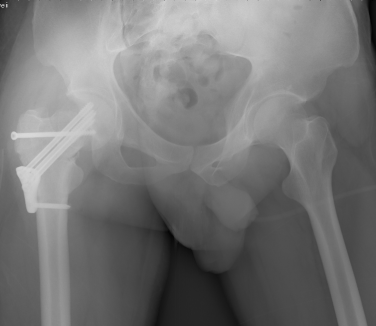

术中拍片

2015年12月,一名32岁的青年男性工作时不慎从高处坠落导致股骨颈骨折(经颈型)而入住我院骨创伤与手外科,考虑该类骨折具有很高的坏死率,患者越年轻坏死率越高。“以往,该类骨折手术的实施主要依靠患者的X光片进行手术分型,但X光片的缺陷主要在于其平面化,因此往往需要医生有一个立体空间的想象力,才能为接下来的手术做好铺垫。”即使行局部骨折三维重建也难以让手术医师有个直观的感觉,无法在体外对其进行术前预演。因患者体重较肥胖,骨折移位明显,为降低患者的股骨头坏死率的发生,科室主任陈跃平教授提出使用3D打印技术的“提前干预”,通过3D打印出他的全仿真患者股骨颈进行手术预演,因为有了预演的经验,最终手术得以精准、迅速完成,耗时较以往少了一半以上,目前创伤骨科已为近10位患者成功实施手术,患者术后恢复良好。

3D打印在骨科应用并推广,因为骨科的专业特点与其技术特点吻合度颇高。借助3D打印,医生可以为患者“量身打造”钢板等内置物,有效解决了传统内置物与骨骼无法完全帖服和适形的难题,术前就可以对既有的钢板进行塑形使得内置物能够更好地发挥固定、支撑或替代作用,也大大地减少了手术时间,减少了手术的创伤,助力我院医疗质量的提升。